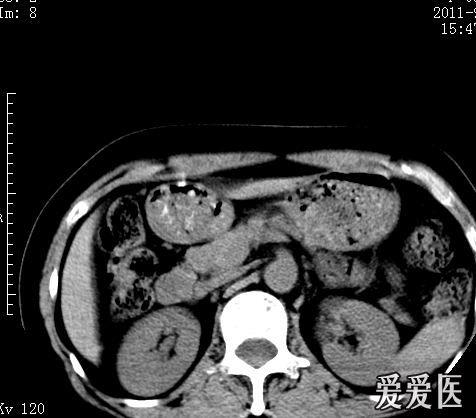

x线检查 多数正常,约1/4发现静脉石(图3),幼年开始患病者眶腔扩大及

静脉石11主要表现为点状的钙化,ct显示清晰,腹部平片